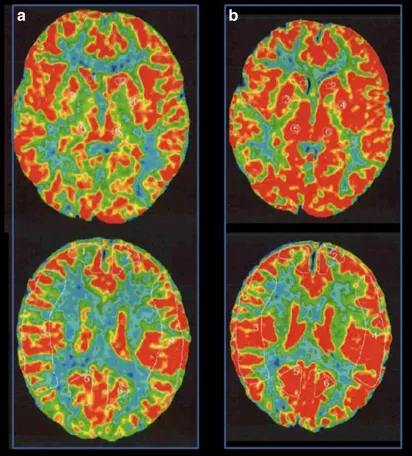

MRI没有发现脑卒中病变,但基底节有多个血流空洞。MRA显示右颅内颈内动脉末端狭窄,左颈内动脉造影显示颈内动脉无狭窄,右大脑前动脉由左大脑前动脉经前连合动脉供血。右颈内动脉造影显示颈内动脉末端狭窄,大脑前动脉缺失,大脑中动脉较左动脉扩张,烟雾血管在颈内动脉顶部形成(图1)。Suzuki期为II期或介于II期和III期之间的过渡期。氙-CT灌注成像技术Xe-CT静息时及负荷时对比,显示右侧大脑中动脉区脑血管反应为14.8%,与左侧相比,右侧大脑中动脉区域的血供摄取没有明显减少(图2)。

图2:术前Xe-CT显示静息状态无偏侧(a),注射丹木斯(Diamox)后右侧MCA区域脑血管反应性为14.8%(b)。